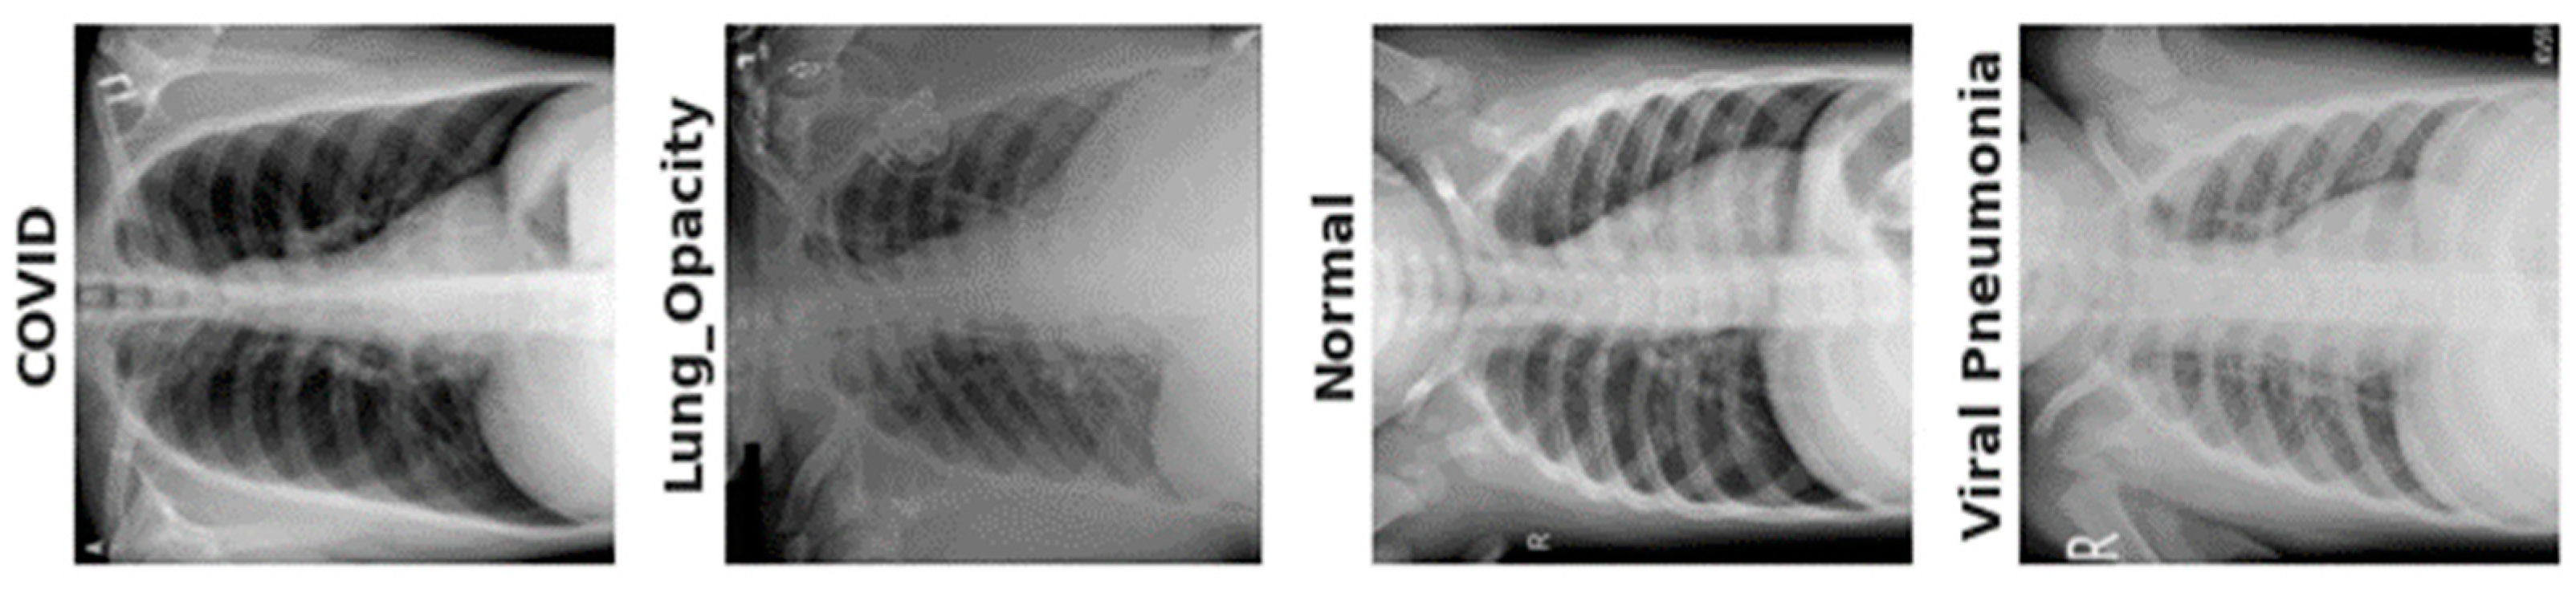

3.1. Data Acquisition

| Category | Images | Data Augmentation |

|---|---|---|

| Normal | 375 | 12,000 |

| Pneumonia | 345 | 12,000 |

| COVID-19 | 375 | 12,000 |

| Lung Opacity | 400 | 12,000 |

| Total | 1495 | 48,000 |